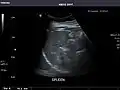

- Spleen

Spleen: Normal in size.